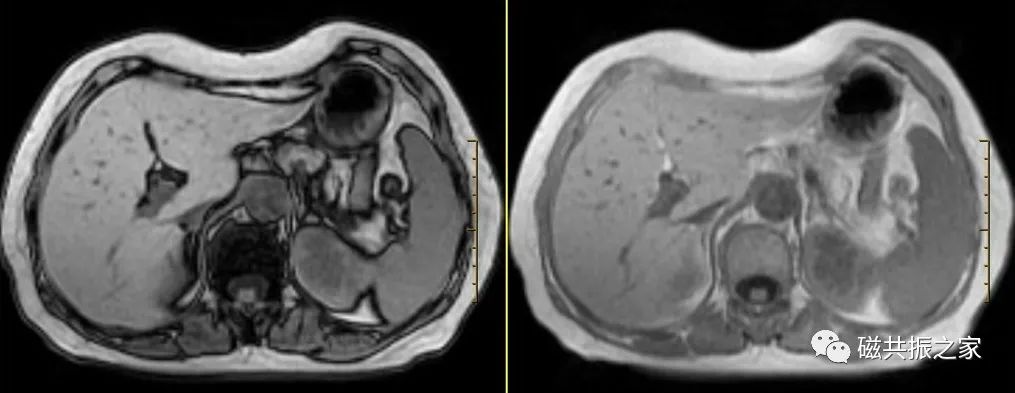

横轴面:横轴面同反相位序列

在矢状位和冠状位上定位。扫描范围包括整个肝脏,根据扫描范围合理调整扫描范围,需包括整个病变范围。

水中的氢质子与脂中氢质子相差3.27ppm,140Hz/T。1.5T上反相位2.4ms 同相位4.8ms,3.0T上反相位1.2ms 同相位2.4ms。

同反相位序列主要用于检测病灶含脂质情况,如脂肪肝,铁过载的鉴别诊断。

对于微小含脂类病变,3D薄层的可靠性更高。